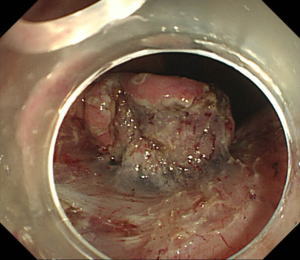

| 【胃ESD】 |

粘膜下層剥離術が終了したところ。大きな合併症はなく終了しました。 |

最大径50mm程度のやや大きめの早期胃癌でしたが治癒切除されていました。 |